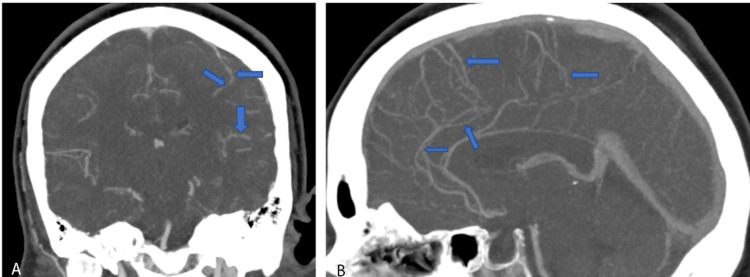

The patient returned within two weeks with worsening thunderclap headaches and blurry vision. Neurologic examination was again unremarkable for any focal neurological deficits. CT Head without contrast was unrevealing for any acute intracranial pathology. CTA Head and Neck with contrast demonstrated multifocal stenosis of intracranial arteries, right greater than left (Figure 2). Given persistent concern for RCVS, the patient was treated with verapamil for symptomatic relief. Following improvement in her symptoms, she was discharged home with the plan for continuation of verapamil and follow-up with neurology outpatient with repeat imaging. She was also extensively counseled to avoid ashwagandha and other stimulants to avoid precipitating RCVS.